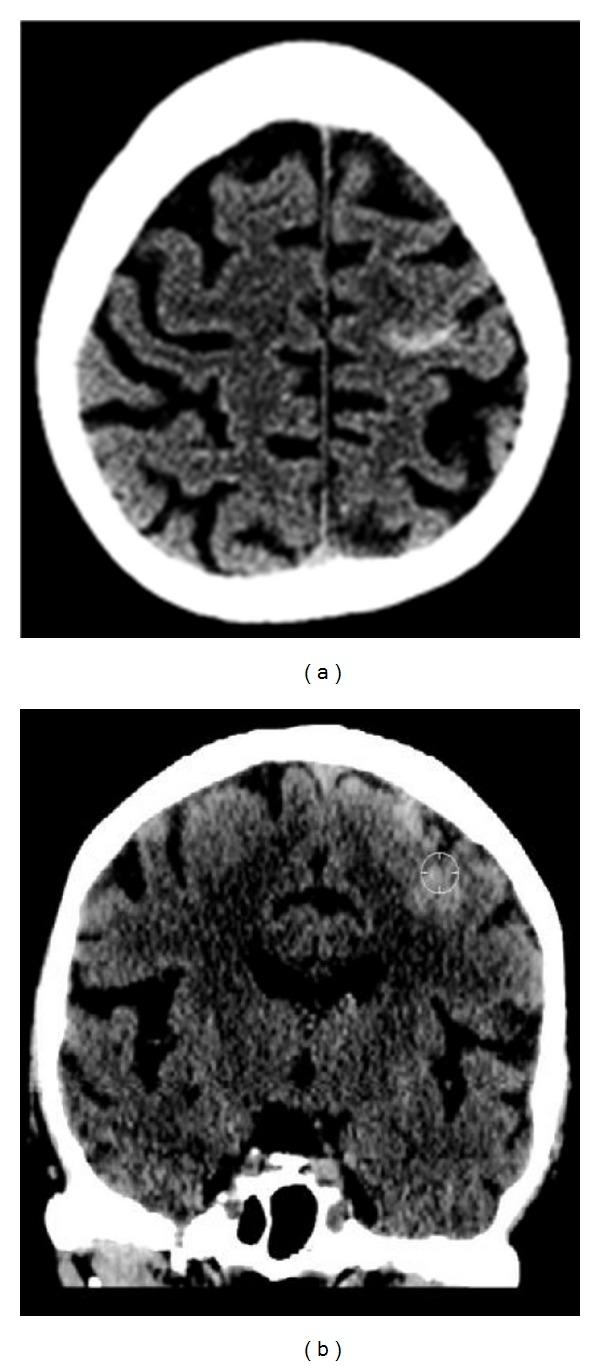

Central sulcus hemorrhage is a rare imaging finding that can be related to cerebral amyloidosis in a normotensive non-traumatic elderly patient and present as an isolated finding or in association with other areas of involvement. We report a case presenting with an isolated central sulcus hemorrhage on computed tomography. Further imaging work-up excluded other potential causes of peripheral hemorrhages and established a putative diagnosis of cerebral amyloidosis.

中央沟出血是一种罕见的影像学表现,在血压正常、非创伤性的老年患者中可能与脑淀粉样血管病相关,可表现为孤立性发现或伴有其他受累区域。我们报告一例计算机断层扫描显示孤立性中央沟出血的病例。进一步的影像学检查排除了外周出血的其他潜在原因,并初步诊断为脑淀粉样血管病。